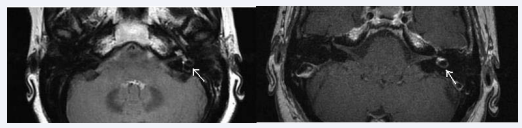

3.0 Tesla MRI was performed for all patients, 1 to 16 days after initial symptoms (mean 4 days) (Figure 3).

Figure 3 MRI of a left ILH: spontaneous hyperintense signal in T1 (left) and FLAIR (right) sequences.

Unilateral ILH was found on MRI in 8 cases, always ipsilateral to cochlear symptoms. No case of multiple etiologies is reported. All patients were treated by 48 hours of intravenous corticosteroids and oral relay, for a total period of 7-10 days.